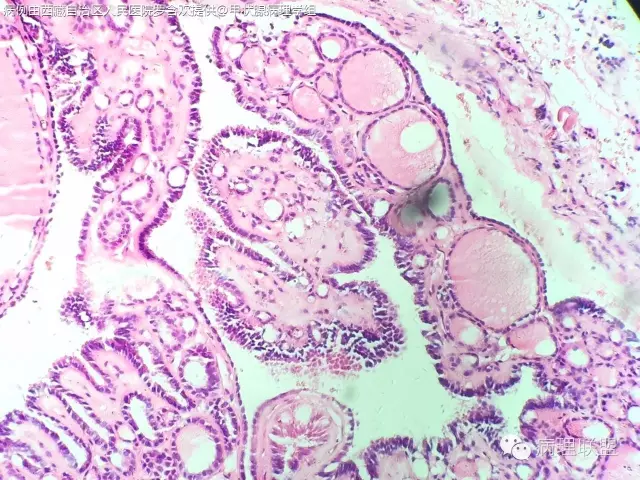

请教老师们一个病例,女,61岁,双侧甲状腺占位。(病例由西藏自治区人民医院 罗含欢 提供,致谢!)

没有看到浸润性生长,仔细看细胞核是否有乳头状癌的特征(核沟、毛玻璃样、加包涵体),图片不是很清楚,目前看上去应该是良性的,没有间质反应和砂粒体。浅见。

核不清,宽厚纤维间质,核重叠,应为乳头状癌

@罗含欢 结节性甲状腺肿伴出血囊性变,部分滤泡上皮乳头状增生

结甲,部分腺上皮乳头状增生

@罗含欢 @周泉 @邓永键 @韩绘宇 这例请几位老师看一下

@毕超 上一例跟你这个不一样。诊断结节性甲状腺肿伴滤泡上皮乳头状增生就可以了。唯一有点怀疑的是那小小灶真的乳头状结构的区域,虽然不是很清楚,但是可以隐约看出其细胞排列相当的整齐,规则。跟你这例完全不一样,核也是位于同一水平,个人看法,不对的地方请老师们指正

第一例乳头内有滤泡,第二例是真正纤维轴心,两例乳头不一样